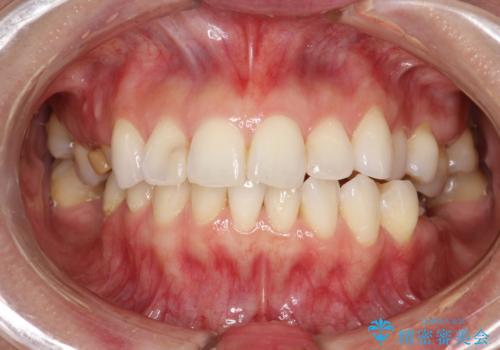

PMTC30分コース(保険外治療)を行いました。かなり久しぶりの歯科医院へ来院とのことで、プラーク(歯垢)・歯石・ステイン(着色)が付着していました。汚れを除去し、本来のご自身の歯質にすることでなにか異常があった際に発見しやすくなります。

PMTCで汚れを除去することは、虫歯や歯周病・口臭予防に効果的です。

また、今回はクリーニング後に、何か所か虫歯や治療途中のままの部分が発見されました。今後は定期的なメンテナンス・クリーニングと併用しながら虫歯の治療を行っていく予定です。